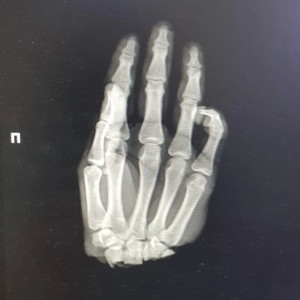

Во Владимирской области 16-летний подросток отрубил себе кисть

Парня спасли нижегородские врачи